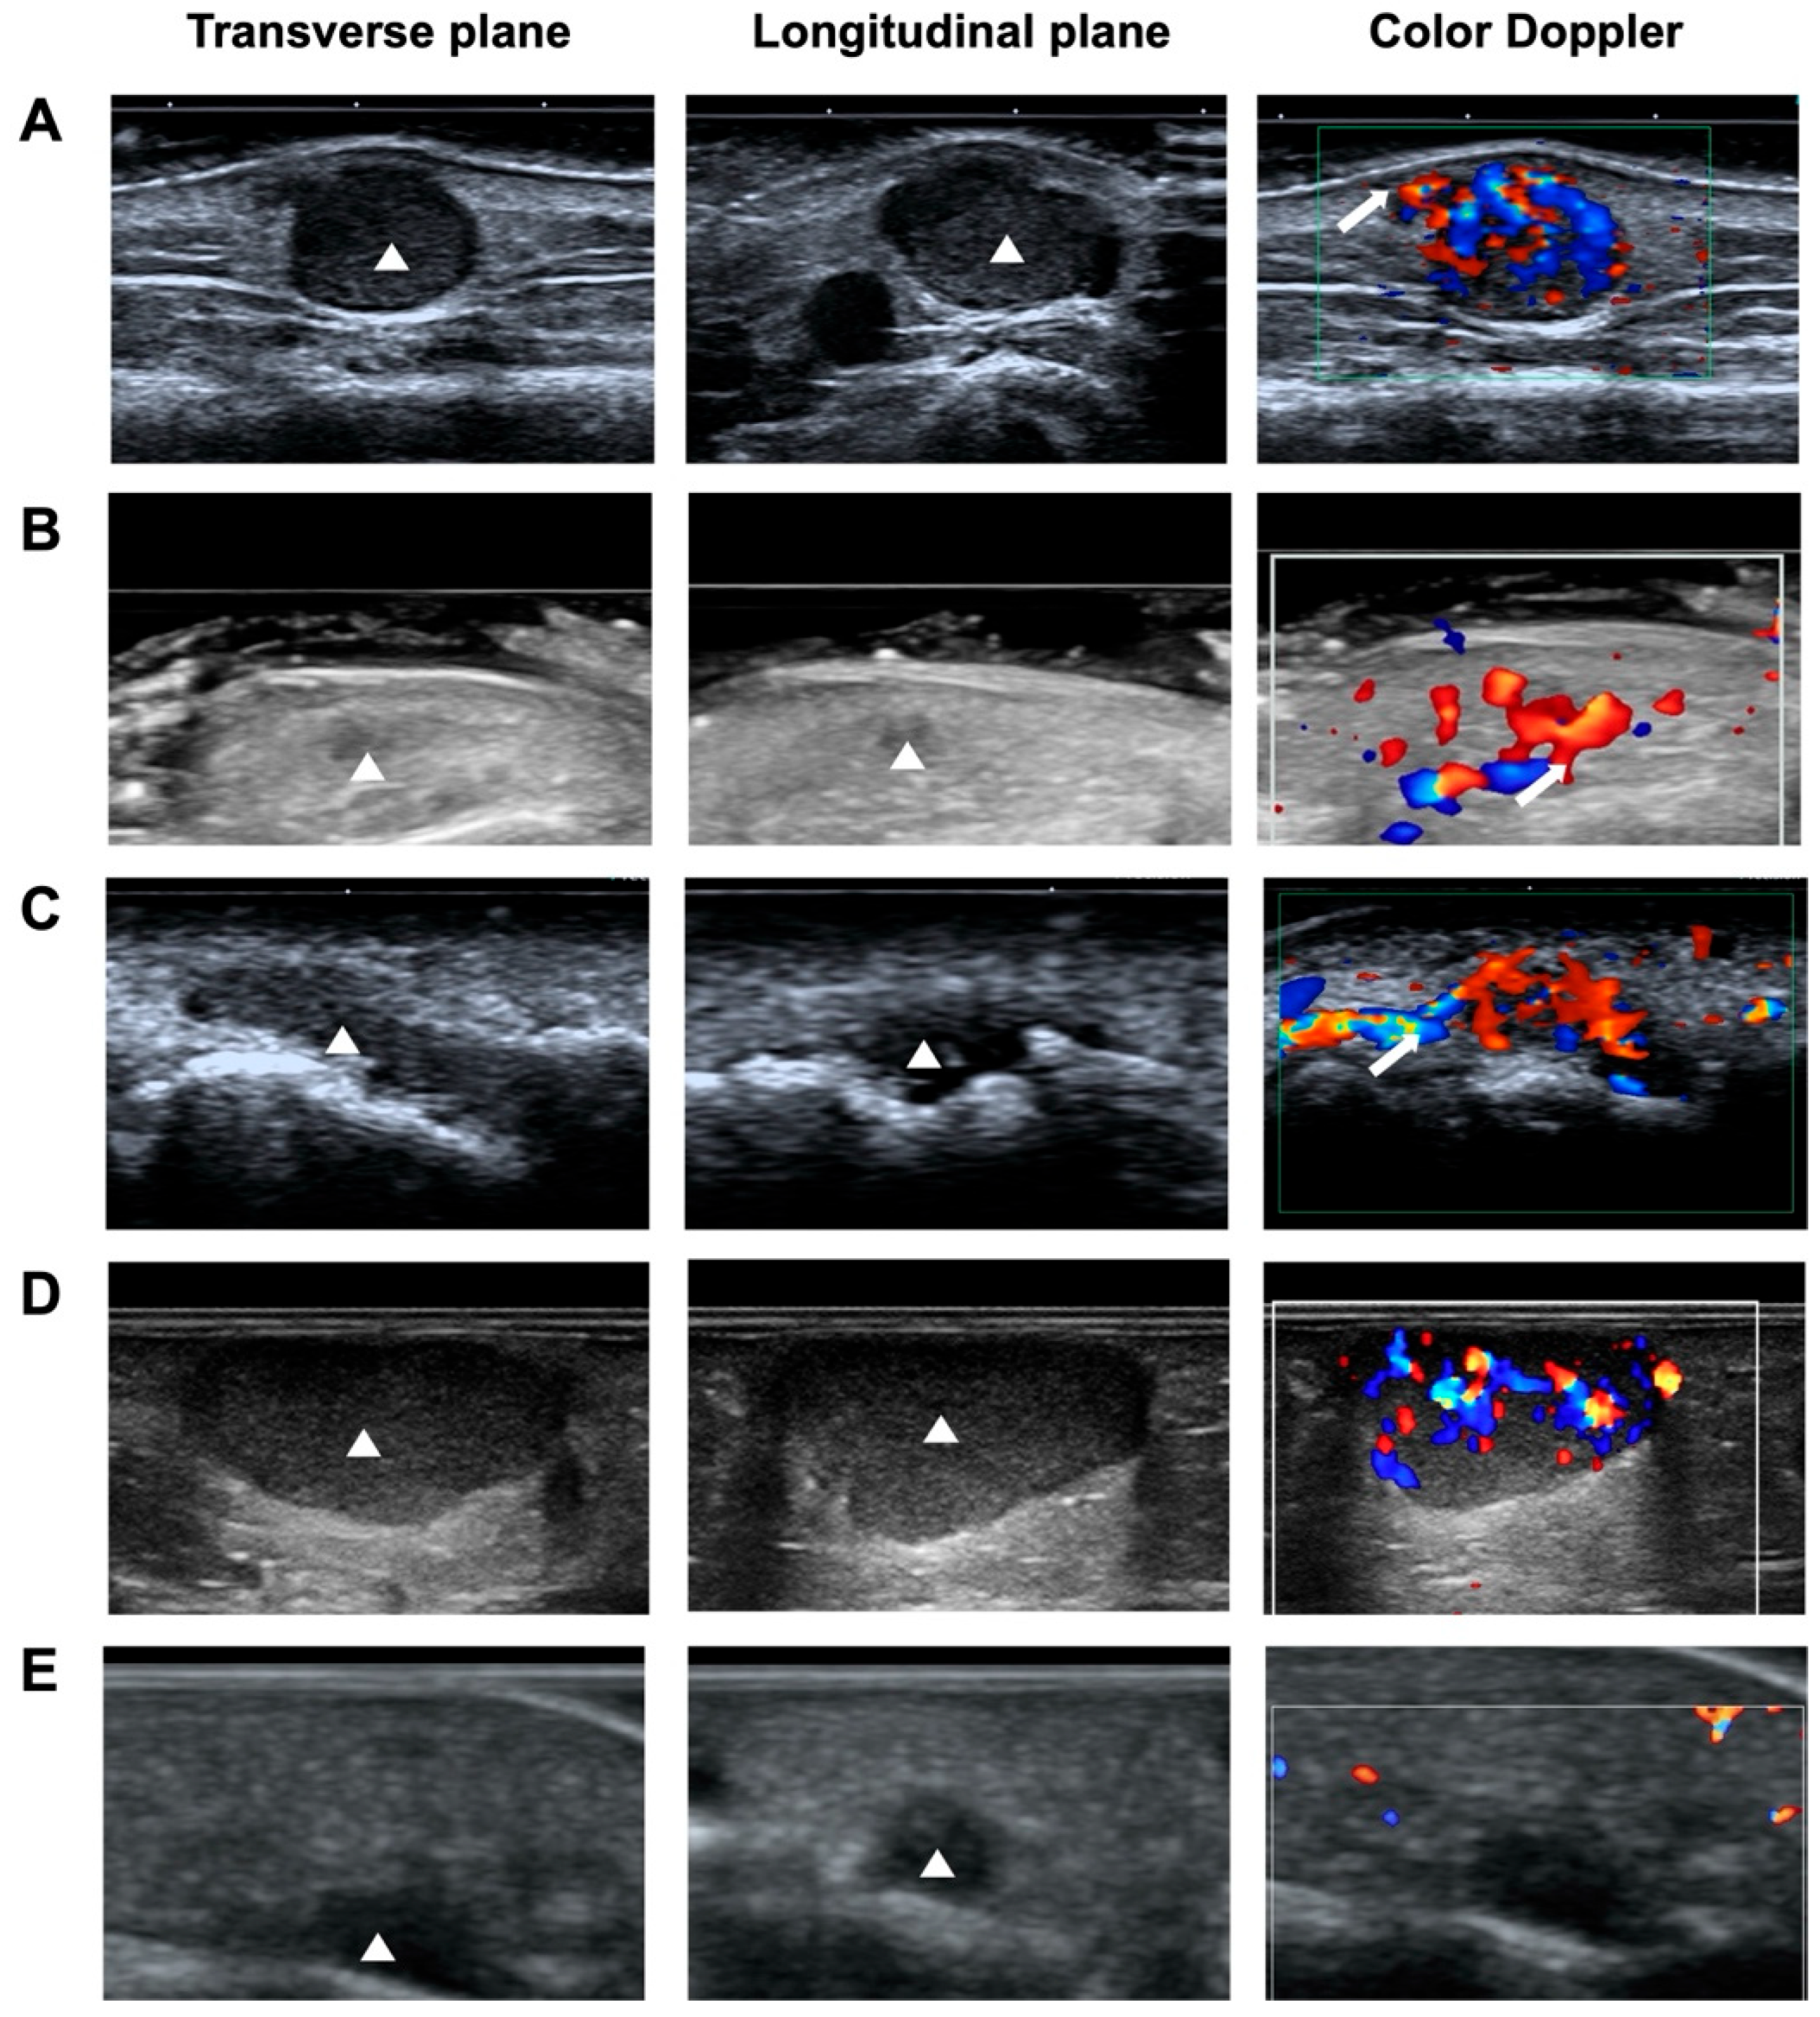

The sonographic features of NSGTs, ALMs, and hemangiomas were summarized in Table 2 and representative sonograms of the three types of diseased were shown in Figure 1. Most of NSGTs (75.86%) and ALMs (94.12%) presented an oval shape. Comparably, 49.25% of hemangiomas presented as irregular, significantly higher than their NSGT and ALM counterparts (p < 0.001). Nearly all the three types of tumors were horizontally orientated, with only one NSGT and one ALM in vertical orientation.

3.4.4. Vascularity

The blood vessel patterns observed by color Doppler ultrasound of these three types of superficial soft tumors could present as no, minimal, moderate, and marked blood-flow signals, with no significant differences (p > 0.05). Interestingly, as reported by Hee-Jin Park et al. [22], vascular stalk sign, reflecting the vascular origin of the tumor (Figure 1A), was observed in 38 NSGT patients (65.52%), significantly higher than that in ALMs (27.94%, p < 0.001) and hemangiomas (16.42%, p < 0.001).

Figure A1. Ultrasound features of NSGTs. (A) NSGT appears as oval-shape, hypoechogenic, well-circumscribed, and hypervascular (with vascular stalk sign). (B) NSGT appears as irregular, hypoechogenic, ill-circumscribed, hypervascular (with vascular stalk sign). (C) NSGT appears as irregular, hypoechogenic, well-circumscribed, hypervascular (with vascular stalk sign). (D) NSGT appearss as oval-shape, hypoechogenic, well-circumscribed, hypervascular (without vascular stalk sign). (E) NSGT appears as irregular, hypoechogenic, ill-circumscribed, avascular (without vascular stalk sign).

Figure 1. Representative gray scale and color Doppler ultrasonograms of NSGT, ALM, and hemangioma. (A) Gray-scale ultrasound images obtained using high-frequency ultrasound show a hypoechoic mass measuring 7 × 3 mm in the subcutaneous tissue in the right arm of a 56-year-old man (yellow arrowhead). Color Doppler ultrasound reveals a hypervascular lesion (grade 3) with a vascular stalk sign (yellow arrow). (B) A hypoechoic mass measuring 15 × 6 mm in the left foot of a 31-year-old man (yellow arrowhead), with vascularity of grade 1. (C) A hypoechoic mass measuring 19 × 6 mm on the right finger of a 36-year-old woman (yellow arrowhead), with vascularity of grade 3.